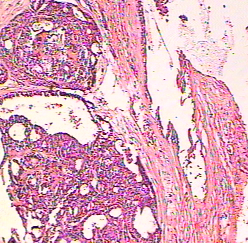

A 63-year-old woman presented with a long-term history of an asymptomatic nodular lesion on her nose. Physical examination revealed an exophitic translucent nodule, 12 mm in diameter, on the base of the nose. Surface telangiectasia was seen on the lesion and there was also scant serous discharge from the lesion .An incisional skin biopsy specimen was obtained from the lesion for histopathological evaluation . The diagnosis is ?

Diagnosis: Eccrine Hydradenoma Nodular hidradenoma, also called clear cell hidradenoma and eccrine spiradenoma is an uncommon sweat gland tumor, found mainly in adult females. The lesions are usually solitary and are most likely to be found on the scalp, face or anterior trunk (1). They are usually covered by intact skin, but some tumors show superficial ulceration and discharge serous material (1). Histologically the tumor is composed of lobulated masses located in the dermis and extending into the subcutaneous fat (2). It is composed of two cell types; the polygonal cells, whose glycogen content may give the cytoplasm a clear appearance, and elongated, darker and smaller cells, which may appear at the periphery. The tumor may be solid or cystic in varying proportions (3). From the clinical point of view, basal cell carcinoma should be kept in mind in differential diagnosis, especially when there is surface telangiectasia as in our case. In treating nodular hidradenoma, complete primary excision is advocated, but our patient refused this decision. References 1. MacKie RM. Tumors of the skin appendages. In: Rook /Wilkinson/Ebling, eds. Textbook of Dermatology. Oxford. Blackwell Science Ltd.1998:1695-1715 2. Elder D, Elentisas R, Ragsdale BD. Tumors of the epidermal appendages. In: Elder D, Elentisas R, Jaworsky C, Johnson B Jr, eds. Histopathology of the Skin. Philadelphia, Pa: Lippincott-Raven Publishers; 1997:747-803 3. Weedon D. Skin Pathology. New York, NY:Churchill Livingstone,1997: 713-755 |